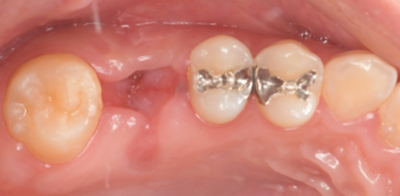

初診時レントゲン(パノラマ)

初診時口腔内写真

初診時パノラマX線写真と口腔内写真。

右上6に腫脹と排膿がみられた。